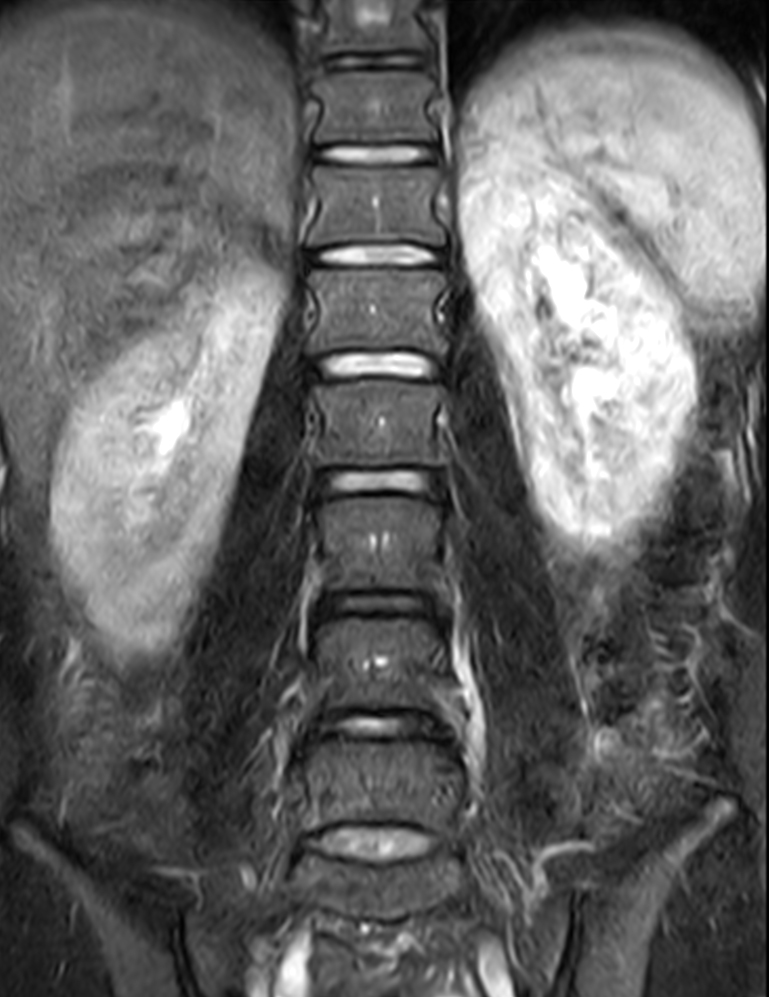

Coronal T2w TSE FatSat